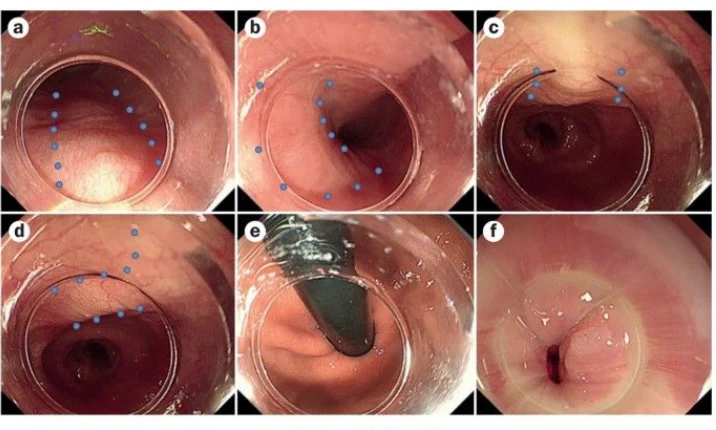

- EMR

- ESD

- Polypectomy